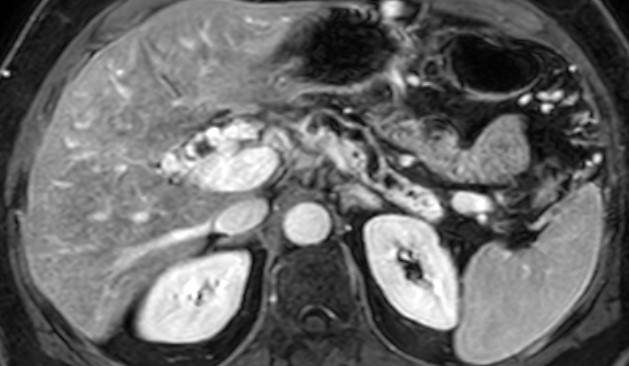

Die MRT der Bauchspeicheldrüse besticht dabei durch ihr Detailreichtum und den besonders hohen Weichteilkontrast. Dadurch eignet sich dieses Verfahren insbesondere zur Beurteilung der Organe unseres Körpers, wie beispielsweise des Pankreas, und ist anderen bildgebenden Verfahren häufig deutlich überlegen.

Meistens wird bei der MRT des Pankreas auch Kontrastmittel (KM) eingesetzt. Dies ist in der Regel gadoliniumhaltig und wird über eine Vene verabreicht. Anschließend reichert es sich in manchen Geweben stärker und in manchen schwächer and, sodass verschiedene anatomische Strukturen am und um das Pankreas hervorgehoben werden. Insbesondere bei der Suche nach Pankreastumoren, die auf den nativen MRT-Aufnahmen nicht schon deutlich abgrenzbar sind kann eine sogenannte „dynamische“ KM-MRT hilfreich sein.

Dabei werden bei angehaltenem Atem mehrere Aufnahmen in verschiedenen Zeiträumen nach der Kontrastmittel-Injektion angefertigt. Verschiedene Tumore zeigen dabei entweder eine rasche, stärkere oder eine verzögerte und geringere KM-Aufnahme als gesundes Pankreasgewebe.